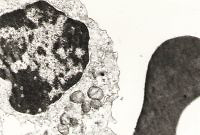

Clinical profile of ocular toxoplasmosis in the Universiti Sains Malaysia Hospital – 7-year review

Tong Jong Haw Matthew,

Embong Zunaina,

Adil Hussein,

Ahmad Tajudin Liza-Sharmini,

Wan Hitam Wan-Hazabbah,

Ismail Shatriah

Family Medicine & Primary Care Review 2018; 20(1): 13–16

Online publish date: 2018-03-16

DOI

:

https://doi.org/10.5114/fmpcr.2018.73698